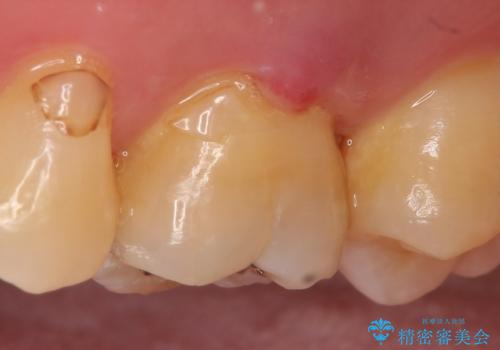

- ものを咬むと痛むので診て欲しいといらっしゃった方の症例です。

数年前に他院にて虫歯治療後しばらく痛みがあったが、やがて治まった。その後何事もなかったが、数か月前からものを咬むと痛むようになったとのこと。

検査の結果歯の神経が死んでいたため根管治療を施し、症状が治まったのを確認後オールセラミッククラウンによる補綴を行いました。